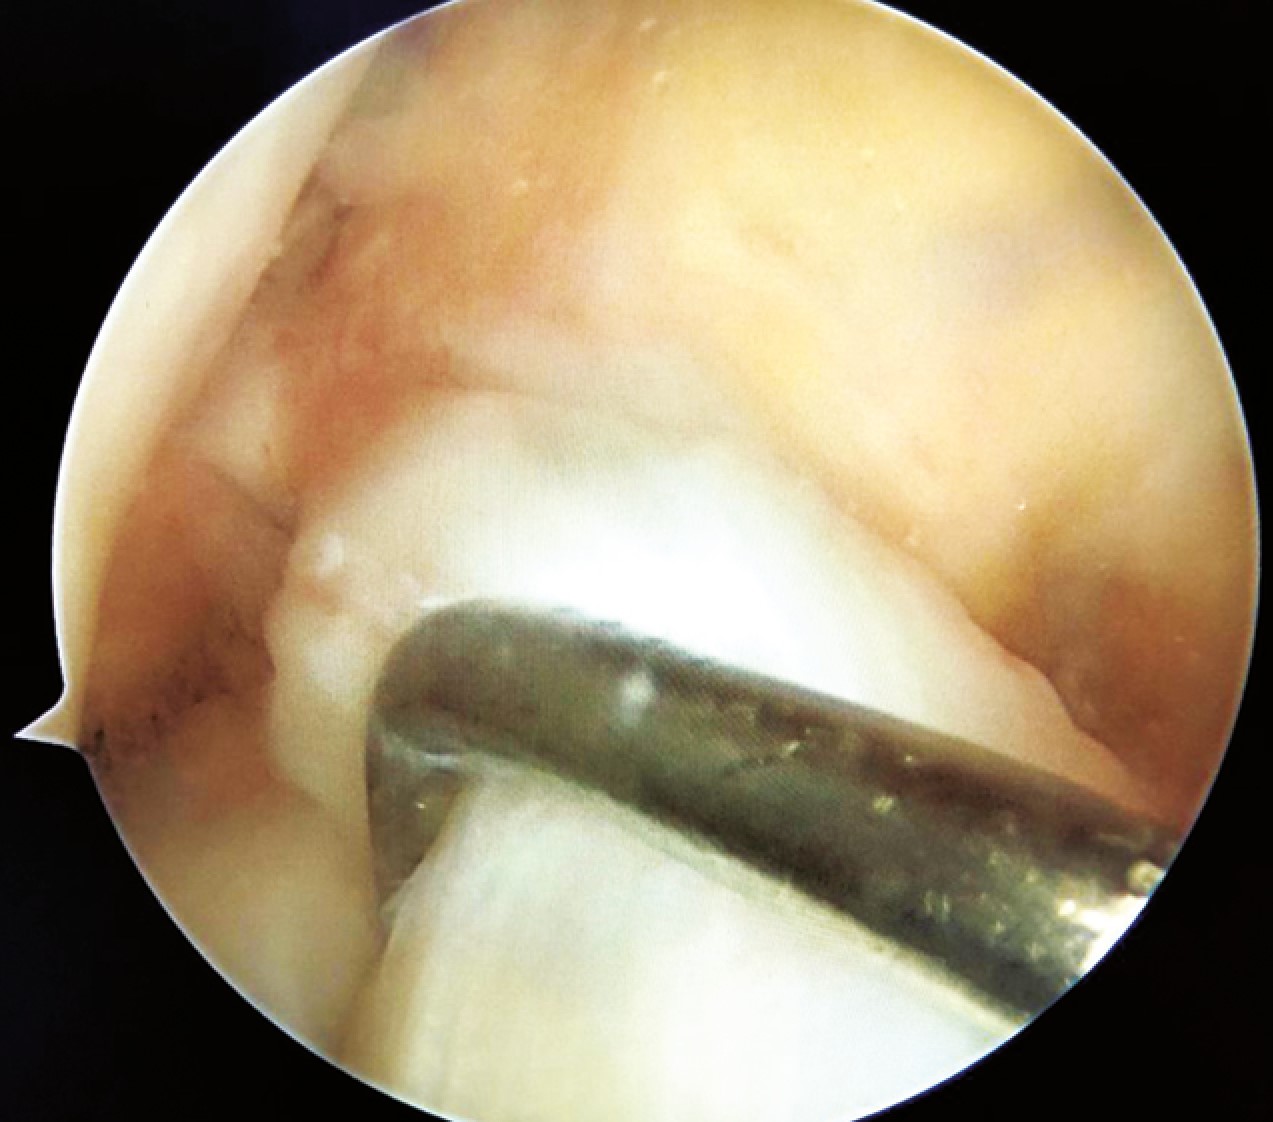

Arthroscopic primary ACL repair was performed using the technique described by G.S. DiFelice et al. [26], involving stitching of the ACL stump with free sutures, preparation of the footprint area until “pinpoint bleeding” appeared, threading the sutures through an anchor loop, inserting it into a pre-prepared bone tunnel, and final fixation after tensioning the sutures and repositioning the ACL stump at the footprint (Figure 4).

Figure 4. Arthroscopic image of the primary ACL repair